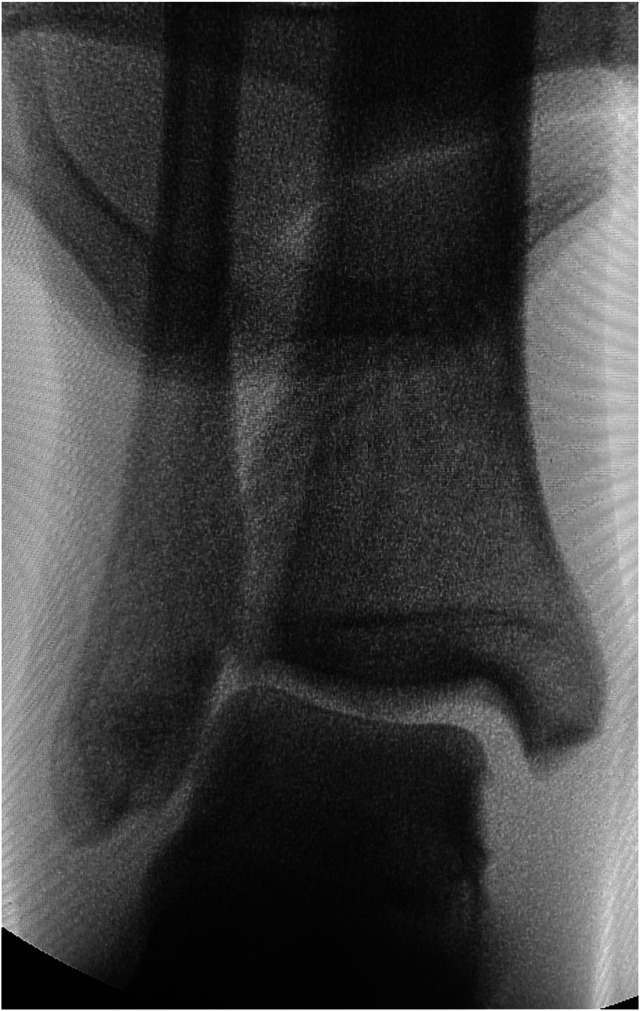

Background: Ankle injuries, often involving the syndesmotic complex, are common and may lead to acute instability. The syndesmosis, comprising several key ligaments, provides critical support for ankle function. This study assesses the efficacy and safety of the suture button system for isolated syndesmotic injuries, a treatment method that is gaining popularity over traditional transsyndesmotic screws.

Methods: A retrospective review was conducted on patients treated surgically with the suture button system for isolated syndesmotic injuries from January 2018 to December 2023. Key outcomes measured included time to full weight-bearing, returning of daily activities, and complications. The study also compared these outcomes with historical data from screw fixation methods.

Results: Thirty-two patients (20 men, 12 women; mean age 41.66 ± 16.57 years [range 16-72 years]) were analyzed over an average follow-up of 9.94 ± 5.49 months (range 3-28 months). Patients achieved full weight-bearing at 1.23 ± 0.31 months postoperatively, resumed daily activities with restrictions at 3 ± 1.09 months, and without restrictions at 6.67 ± 2.55 months. No major complications were reported; minor complications included implant removal due to irritation in two patients (6.25%) and minor wound issues in one patient (3.13%).

Conclusion: The suture button system demonstrated good outcomes in allowing physiological motion, low malreduction rates, and minimizing reoperation needs. The present results indicate a promising safety profile and functional recovery, despite limitations such as small sample size and lack of patient-reported outcome measures.